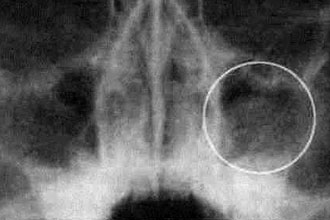

Кисты, опухоли

Магнитно-резонансная томография (МРТ) носовых пазух позволяет получить информацию о различных образованиях в тканях, не входящих в нормальную анатомию. В ходе исследования можно:

- Обнаружить кисты и опухоли.

- Разграничить опухолевую ткань от вторичных воспалительных процессов.

- Точно определить границы новообразования.

Основная задача МРТ – различение опухоли, реактивного выпота и отёка слизистой оболочки.

МРТ визуализирует мягкие ткани и позволяет оценить наличие воспалительного экссудата. В некоторых случаях требуется сочетание с компьютерной томографией, которая выявляет изменения в костных структурах. Результаты МРТ помогают врачу более эффективно планировать этапы хирургического вмешательства, оценивать возможные осложнения и прогнозировать исход операции.

Одним из ключевых преимуществ МРТ является более детальная визуализация новообразований по сравнению с рентгеновскими снимками и компьютерной томографией. Это связано с тем, что вокруг опухолей образуется зона реактивного воспаления, увеличивающая площадь патологических изменений на рентгенограммах и КТ. Однако при МРТ удаётся четко различить сигналы воспалённых тканей и опухолевых образований.